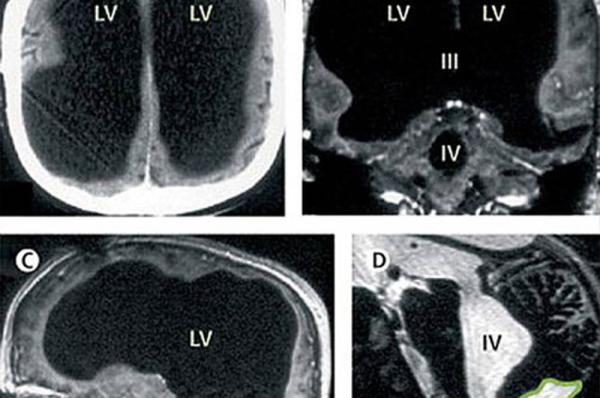

X光片显示,该男子75%的脑组织已消失不见。

据英国媒体报道,法国一名男子曾因腿部疼痛去医院检查,医生却找不出病根。在对其进行了全身体检后才发现,原来这名男子的腿疼是由脑部病变引起的,而该男子的大脑只剩下正常人大脑体积的一半都不到了。

报道称,这件事其实发生在2007年,近日由著名医学杂志《柳叶刀》披露。这名大脑神秘消失的男子当年44岁,医生在对其进行脑部检查后发现,他左右半脑上的额叶、顶叶、颞叶及枕叶都萎缩了。

在对这名男子的病史进行详细调查后发现,原来他童年时患有后天脑积水症。但在他14岁时,经历了分流术,随后的30年,这名男子和家人都以为完全康复了。但其实他的大脑还是在病变,最终,脑内的积水损坏了脑组织,导致其大脑50%至75%的部分都消失了。